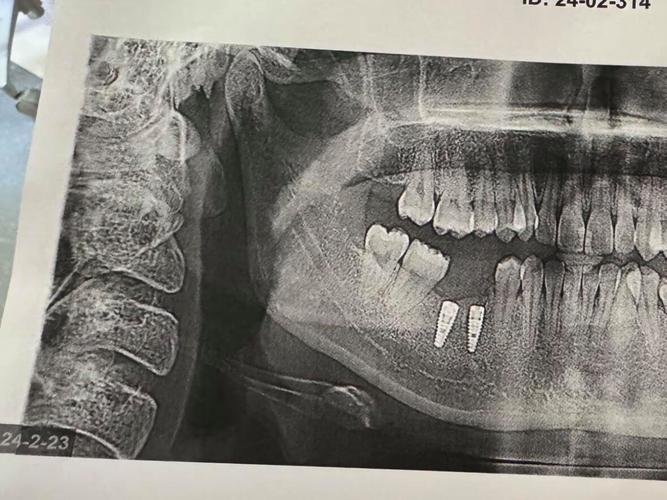

Straumann® BLX作为新一代明星产品,采用“锥形+平台转移”设计,通过种植体基台的错位对接,减少边缘骨吸收,5年随访数据显示骨吸收量平均控制在0.2mm以内;而Straumann® Roxolid则凭借其卓越的材料性能,成为即刻种植和全口负重术式的首选,临床10年成功率高达98.5%。

- 术后随访与维护:术后1周、1个月、3个月、6个月定期复查,通过影像学检查评估骨结合情况,后期每年1-2次专业维护,确保种植体长期稳定。